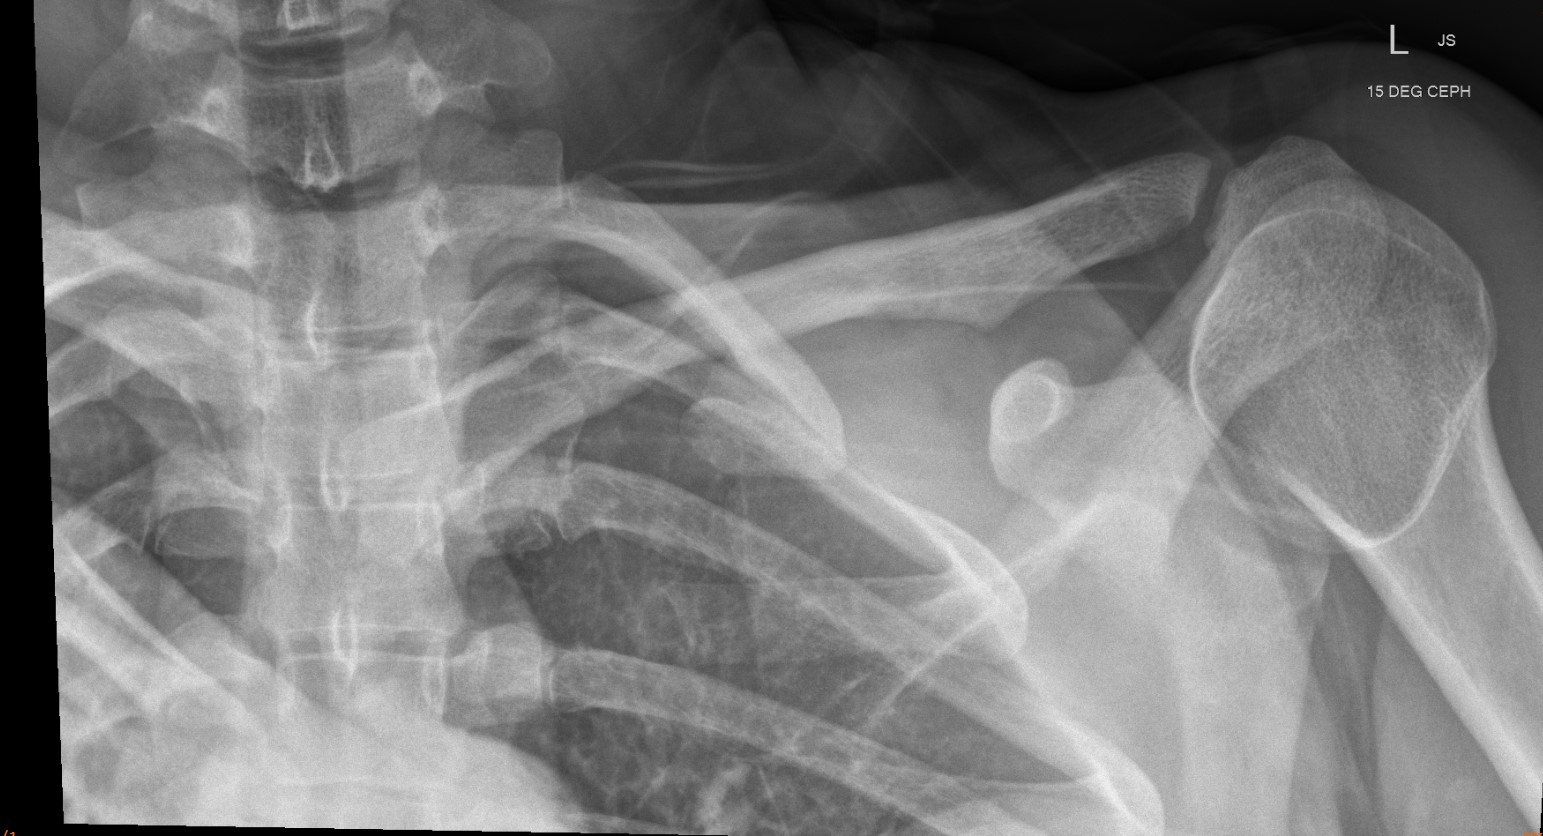

Xray

Can be missed on a xray

CT scan

Left posterior SCJ dislocation with pre- and post angiogram

Left posterior SCJ dislocation with pre- and post angiogram

Severe left posterior SCJ dislocation with subclavian vein compression